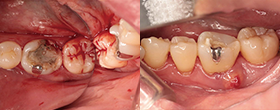

XPエンドシェイパーとエッジシークエルサファイアを使用

XP-Endo Shaper(白水貿易)+EdgeSequel Sapphire™ in MB1 & MB2

エッジシークエルサファイアを使用

#35/.04 EdgeSequel Sapphire™

Case2 直線根管

• CC「左下奥違和感」主訴に来院

左下6遠心根に透過像認める

• インレー除去

透過像に一致した部位にサイナストラクト認める

• コンポジットレジンにて隔壁作成

• 作業長確認

最終拡大#30/.04テーパー